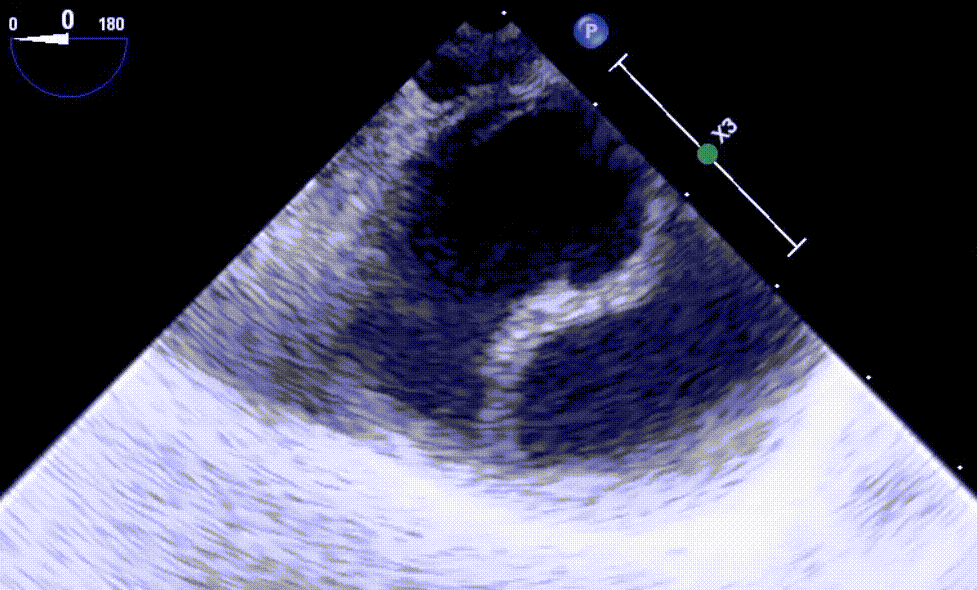

Mid Esophageal 4 Chamber View

To obtain this view the TEE probe is advanced to the

mid-esophagus behind the LA.

The sector depth should be 14cm and omniplane of 0-10°.

Here we visualize: Left Atrium (LA), Right Atrium (RA), Left Ventricle (LV) [inferoseptal (IS) + anterolateral (AL) walls], Right Ventricle (RV), Mitral Valve [anterior(AMVL), posterior (PMVL) leaflets], Tricuspid Valve [Septal (STVL), Anterior (ATVL) leaflets]